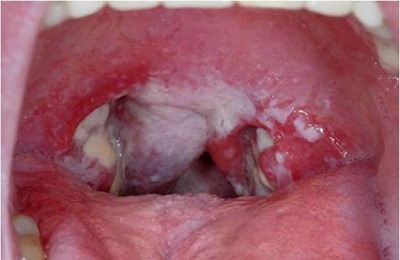

- Дифтерия – проявляется в виде пленки белого цвета на лимфатических узлах горла. Кроме этого сопровождается такими симптомами: высокая температура тела, недомогание, головная боль, тошнота, увеличение лимфатических узлов.

Дифтерия

Характерные симптомы заболевания обязательно требуют врачебного осмотра. После установления диагноза, дифтерию нужно как можно раньше начать лечить. Если запустить болезнь, может произойти поражение нервной системы вплоть до летального исхода.

Данное инфекционное заболевание требует изоляции больного и помещения его в карантин.

Врач берет мазок из горла для вычисления природы светлых комочков в зеве.

Такой анализ позволит узнать, какой из трех типов палочки угрожает жизни человека.

После получения результатов специалист назначает лечение. Чаще всего в таком случае назначают не только курс медикаментов, но и специальное питание.

Обязательно больному прокалывают пенициллин и дают успокоительное. Также вводят сыворотку, которая должна вывести токсины из организма и снять заражение.